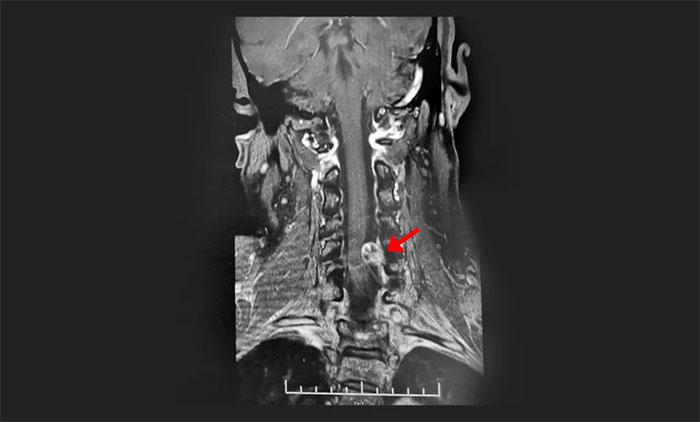

脊髓肿瘤(Tumor of Spinal Cord)亦称椎管内肿瘤,是指生长于脊髓及与脊髓相近的组织,包括神经根、硬脊膜、血管、脊髓及脂肪组织等的原发、继发肿瘤。可分为脊髓内及脊髓外肿瘤。原发脊髓肿瘤每年新发病例2.5/10万,大约是脑肿瘤发病率的1/10。在组织发生学上...[详细]